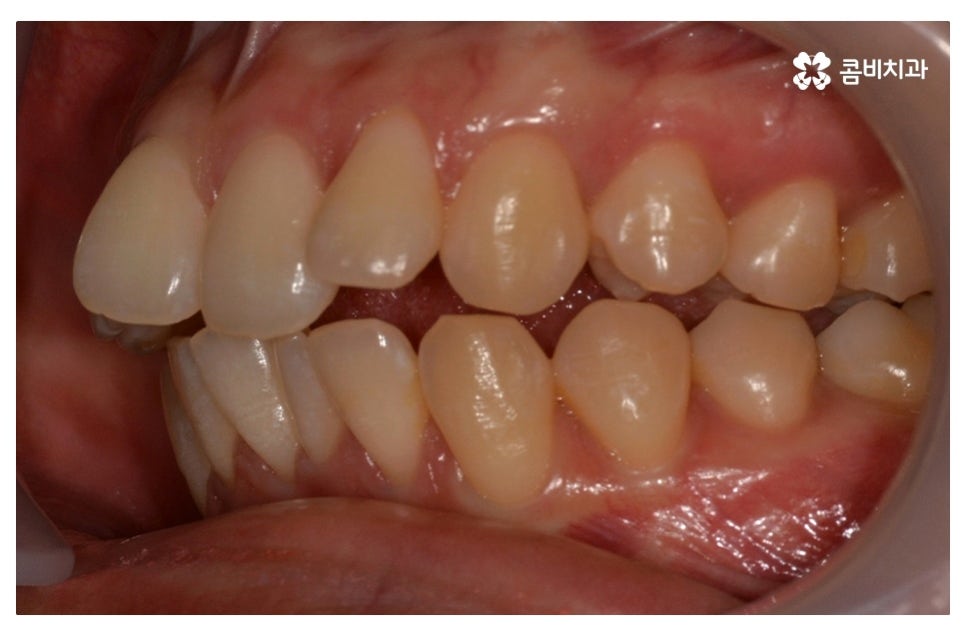

덧니교정은 개인에 따라서 치료 계획이 달라질 수 있는데

덧니의 정도가 사람마다 다르고 구강 구조, 얼굴형, 교합 등을

종합적으로 파악하여 치료 계획을 세울 필요가 있어요.

덧니로 인해 고민하는 분들 중에서 돌출입을 개선하고자

하는 분들도 많고 부정교합이 있는 분들도 많기 때문에

치아의 이동 공간과 치아 이동으로 인한 얼굴 변화, 교합 등에

대해서 면밀한 파악이 중요하다고 할 수 있는데요.

요즘은 교정 장치의 선택에 있어서 다양한 선택이 가능하지만

보편적으로는 본 포스팅의 사례처럼 클리피씨 교정이 많이 선호되고 있어요.

클리피씨 교정은 일반적인 교정보다 치료 기간을 단축시킬 수 있고

통증이 비교적 적으며 세라믹 재질로 심미적이라는 장점이 있어요.

위 환자분의 경우 덧니교정에 걸린 치료 기간은 약 24개월 정도이며

성인 이후에 치료를 진행한 사례라고 볼 수 있어요.